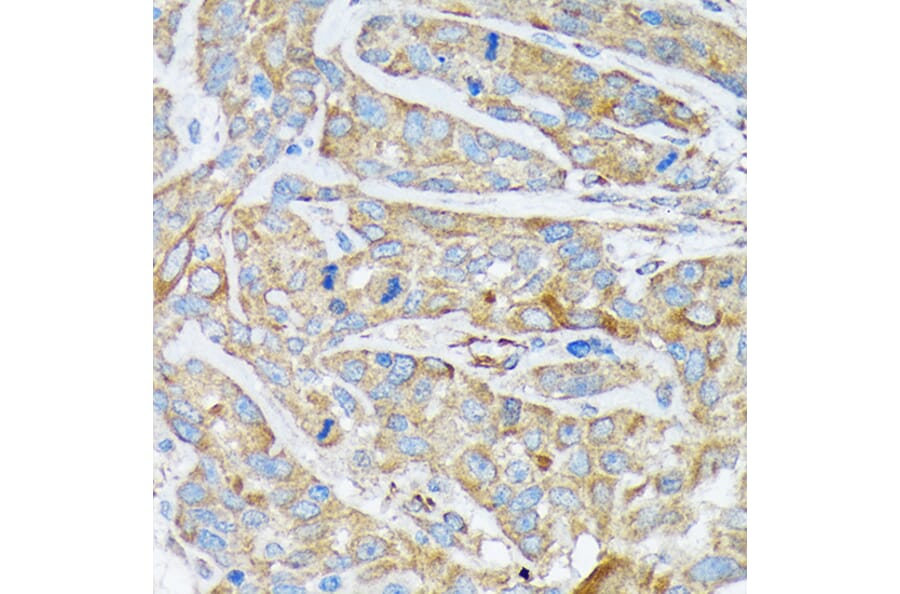

Immunohistochemistry analysis of paraffin-embedded human esophageal cancer using Anti-Cytokeratin 1 Antibody [ARC1745] (A306008) at a dilution of 1:100 (40x lens). Perform microwave antigen retrieval with 10 mM Tris/EDTA buffer pH 9.0 before commencing with IHC staining protocol.